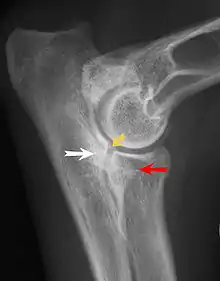

Most primary lesions are related to osteochondrosis, a disease of the joint cartilage, and osteochondritis dissecans (OCD), the separation of a flap of cartilage on the joint surface. Other common causes of elbow dysplasia include an ununited anconeal process (UAP) and fragmented or ununited medial coronoid process (FCP or FMCP).[1]

In OCD, the normal change of cartilage to bone in the development of the joint fails or is delayed. The cartilage continues to grow and may split or become necrotic. The cause is uncertain, but possibly includes genetics, trauma, and nutrition (including excessive calcium and decreased vitamin C intake).[4] OCD lesions found in the elbow at the medial epicondyle of the humerus are caused by disturbed endochondral fusion of the epiphysis of the medial epicondyle with the distal end of the humerus, which may in turn be caused by avulsion of the epiphysis.[5] Specific conditions related to OCD include fragmentation of the medial coronoid process of the ulna (FMCP) and an ununited anconeal process of the ulna (UAP). All types of OCD of the elbow are most typically found in large breed dogs, with symptoms starting between the ages of 4 and 8 months.[4] Males are affected twice as often as females. The disease often affects both elbows (30 to 70 percent of the time), and symptoms include intermittent lameness, joint swelling, and external rotation and abduction of the paw.[6] Osteoarthritis will develop later in most cases.

UAP is caused by a separation from the ulna of the ossification center of the anconeal process.[7] FMCP is caused by a failure of the coronoid process to unite with the ulna.

Diagnosis is through x-rays, arthroscopy or CT (computed tomography). In cases with significant lameness, surgery is the best option, especially with UAP. However, conservative treatment is often enough for cases of FMCP and OCD of the medial humeral epicondyle. The dogs are exercised regularly and given pain medication, and between the ages of 12 and 18 months the lameness will often improve or disappear.[4] Control of body weight is important in all cases of elbow dysplasia, and prevention of quick growth spurts in puppies may help to prevent the disease.

Surgery for FMCP consists of removal of cartilage and bone fragments and correction of any incongruity of the joint. Reattachment of UAP with a screw is usually attempted before the age of 24 weeks, and after that age the typical treatment is removal of the UAP.[8] Without surgery, UAP rapidly progresses to osteoarthritis, but with FMCP osteoarthritis typically occurs with or without surgery. Osteoarthritis is also a common sequela of OCD of the humerus despite medical or surgical treatment.[8] Elbow replacement surgery has been developed and can be an option for treatment.[9]